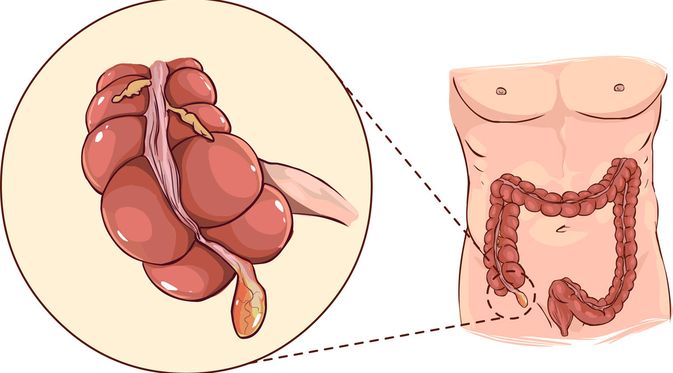

Cari Tahu Letak Dan Penyebab Usus Buntu

Cari Tahu Letak Dan Penyebab Usus Buntu

Yuk Kenali Radang Usus Buntu Rsud Bangkinang

Yuk Kenali Radang Usus Buntu Rsud Bangkinang